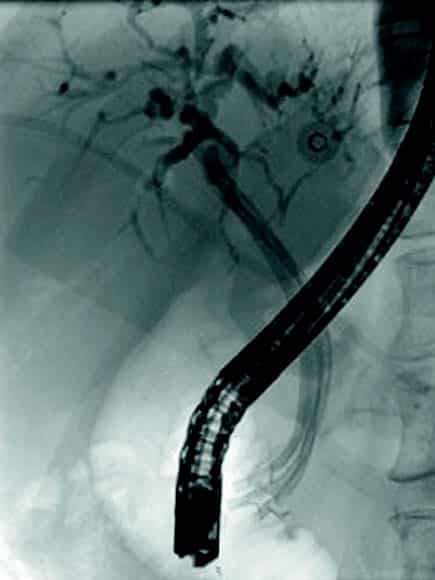

Obstruksjon av gallegang

Inflammasjon og fibrose i caput av pankreas kan skade gallegang og føre til benigne strikturer og kolestase. Slike strikturer kan være krevende å behandle. Det er viktig med god bildediagnostikk i forkant av terapi for å utelukke malign striktur, noe som kan være vanskelig på grunn av de inflammatoriske/fibrotiske forandringene sekundært til kronisk pankreatitt. Det er svært viktig at man ikke intervenerer endoskopisk dersom usikkerhet om malign etiologi men henviser til senter med HPB kirurg og MDT vurdering. Standard behandling av benigne strikturer har vært ERCP med gjentatte dilatasjoner og innleggelse av multiple plaststenter i gallegang over en periode på ett år (Fig 5). De senere år har bruk av selvekspanderende metallstent i 6-12 mnd. blitt mer vanlig dersom forholdene teknisk ligger til rette for dette. Det er imidlertid risiko for residiv av striktur på grunn av progresjon av grunntilstanden så gjentatt endoskopisk behandling kan bli nødvendig.

Fig 5: Pasient med gallegangsstriktur sekundært til kronisk pankreatitt som behandles med endoskopisk ballong dilatasjon og stenting av gallegang.